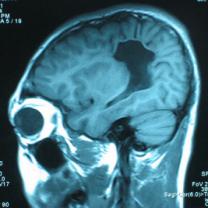

頭顱CT和MRI可見顱骨缺損區(qū)下方軟腦膜囊腫、腦軟化灶或腦室穿通畸形(圖2)。

圖2:①和②CT及骨窗相顯示右頂部顱骨缺損,其下方腦組織呈低密度改變;③-⑥MRI右頂局部顱骨缺如,腦組織輕度向外膨隆,右頂葉側(cè)腦室體部旁局部腦組織缺如,代之以囊性長T1、長T2信號。